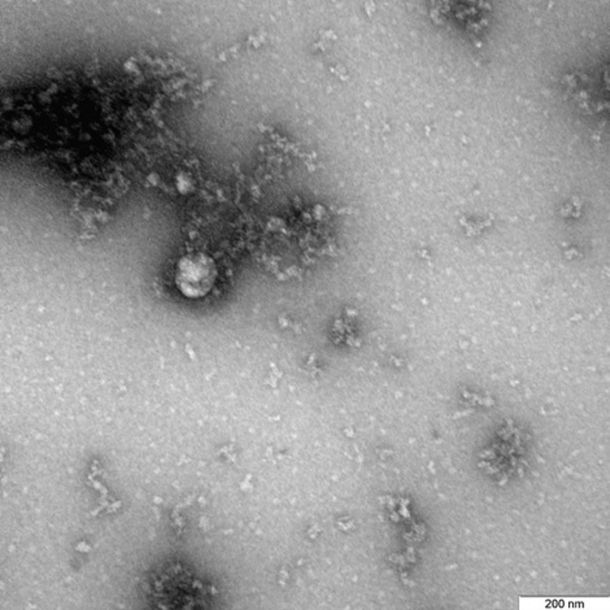

Rusia: lograron fotografiar la cepa británica del Covid-19

El Gobierno de Rusia anunció que pudo tomar la primera foto de la variante del Covid-19 detectada en el Reino Unido, que podría ser más mortal que la original.

El Servicio federal para la Supervisión de la Protección de los Derechos del Consumidor y el Bienestar Humano de Rusia (el Rospotrebnadzor) anunció este lunes que se logró tomar la primera foto de la variante del nuevo coronavirus que fue detectada por primera vez en Kent, sur del Reino Unido. Tras confirmarse que la "cepa británica" es más contagiosa que la que causó la primera ola de la pandemia de Covid-19, las autoridades de ese país sostienen que además podría ser más mortal.

Días después de que el Gobierno de Rusia anunciara que tiene una segunda vacuna contra el coronavirus casi lista, la EpiVacCorona, un equipo del centro de virología y biotecnología Véktor, donde se desarrolló esa fórmula, mostró la primera foto de la variante británica, que fue aislada de un paciente en diciembre de 2020.

"La fotografía del virus bajo el microscopio fue obtenida en el marco del estudio continuo de las características de esta variante del nuevo coronavirus, incluidas sus particularidades estructurales y manifestaciones en culturas celulares y modelos experimentales con el uso de animales de laboratorio", informó el Rospotrebnadzor en un mensaje reproducido por el sitio Actualidad RT.